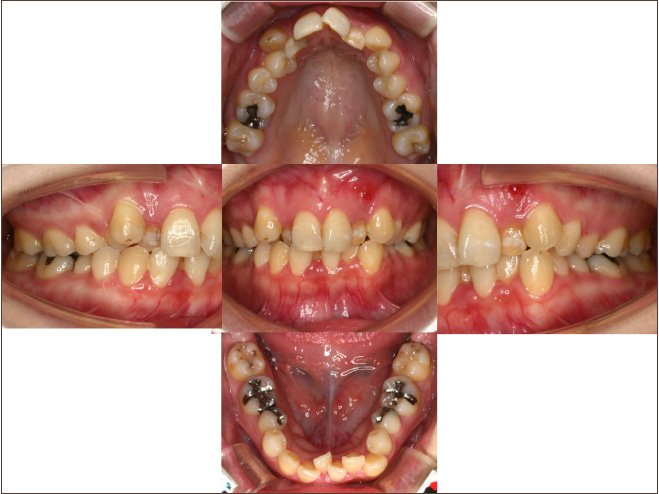

狭い歯列(狭窄歯列)によって、舌が歯列の中に収まらない状態です。

●高口蓋 ●低位舌 ●口呼吸

狭窄歯列(高口蓋)

狭窄歯列(低口蓋)

狭窄歯列(低位舌)

右のように、狭窄歯列だと舌は、狭い歯列に阻まれて、前方や上方の口蓋に自由に動くことができません。その結果、舌は低い位置(低位舌)にあり、前方に出ず後方に位置するので、気道が狭くなってしまっています。

一方、左のように、広い歯列だと舌は、前方にも上方にも自由に動けるので、舌は普段は口蓋についていて鼻呼吸が無理なくできているのです。

狭い歯列(狭窄歯列(きょうさくしれつ))

高口蓋(上顎が深い→鼻腔が狭い)

舌が歯列に納まらない→低位舌

歯並びが悪い

かみ合わせが悪い